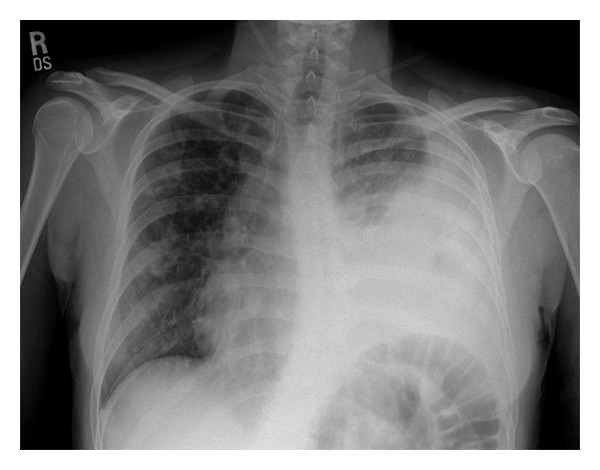

Input 3: What is seen in the X-ray and what should be done?

Image:

- Visual Med-Alpaca: Bilateral infiltrates and bilateral pleural effusion seen in a chest x-ray may indicate a respiratory infection or other respiratory conditions such as pneumonia pulmonary edema, or pleural effusion, it is important to consult a medical professional for a proper diagnosis and treatment plan.

- VQA Medical Model: the decubitus

- Automatic Radiology Report Generation (Image-only): near complete opacification of the left hemi thorax with only a small amount of residual aerated lung in the left upper lobe .